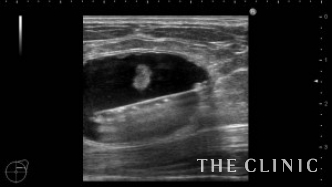

オイルシストはエコー下に穿刺吸引して、消失しました。混合性のしこりは、脇に3㎜程の入り口を作り、そこからしこりにベイザーリポ(ベイザー脂肪吸引)を当てて脂肪塊を崩して吸引除去します。まずは、しこりのカプセル内に麻酔を注入し(左図)、ベイザーリポで脂肪塊を崩します(右図)。